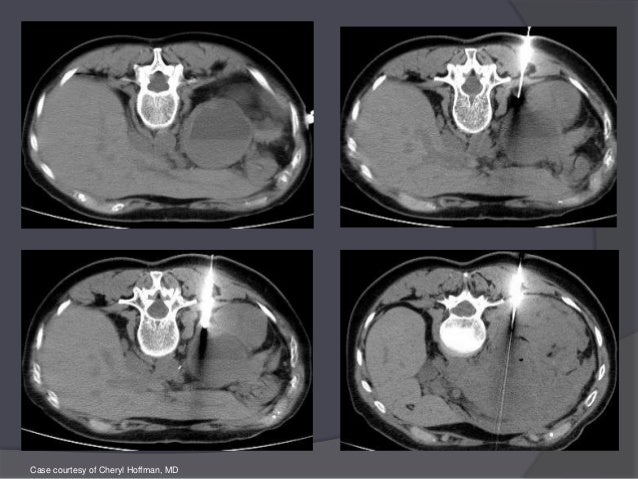

1 25 Mm Thick Ct Image Of Corona Mortis Download Scientific Diagram

www.researchgate.net